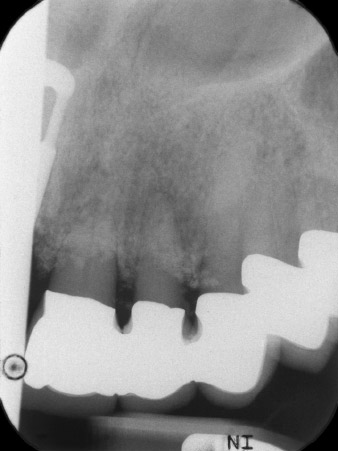

esiti radiologici iniziali

Fig. 1: Gli esiti radiologici iniziali hanno rivelato la necessità di sostituire una ricostruzione protesica eseguita mediante corona splintata. Quando la protesi è stata rimossa, sono stati estratti involontariamente anche i denti 21 e 22.

L'esito radiologico ha rivelato perdita di tessuto osseo in orizzontale attorno ai denti 21 e 22 (Fig. 1). Quando si è passati a rimuovere la corona, questi stessi denti sono stati estratti involontariamente.